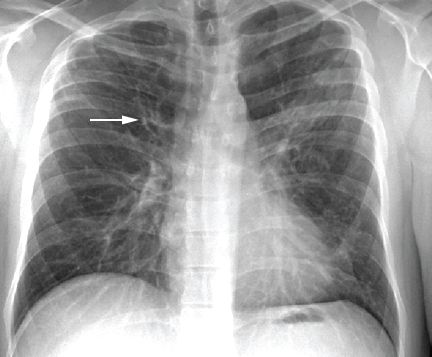

Giãn phế quản là một sự giãn nở vĩnh viễn và dày lên của đường hô hấp đặc trưng bởi ho mãn tính, tạo đờm quá mức, chế độ tồn tại của vi khuẩn, nhiễm trùng cấp tính và tái phát. Nó có thể phổ biến rộng rãi trên khắp phổi hoặc một vùng. Nguyên nhân là do tình trạng viêm mạn tính của đường hô hấp, và có liên quan, hoặc gây ra bởi một số lượng lớn các bệnh. Nó có thể phát triển sau khi nhiễm trùng phổi, đặc biệt ở trẻ em và gắn với các vấn đề cơ bản, chẳng hạn như suy giảm miễn dịch và bệnh xơ nang.

Đường hô hấp bị ảnh hưởng đang viêm và dễ dàng suy yếu. Có sự giảm luồng không khí và thoát chất tiết, dẫn đến sự tích tụ số lượng lớn các chất nhầy trong phổi. Chất nhầy thu thập vi khuẩn, nguyên nhân nền để nhiễm trùng đường hô hấp dưới thường xuyên và thường nặng. Mức độ nghiêm trọng của chứng giãn phế quản thường được phân loại theo khối lượng đờm nhưng nay phần lớn được thay thế bằng sự xuất hiện dấu hiệu trên CT scan.